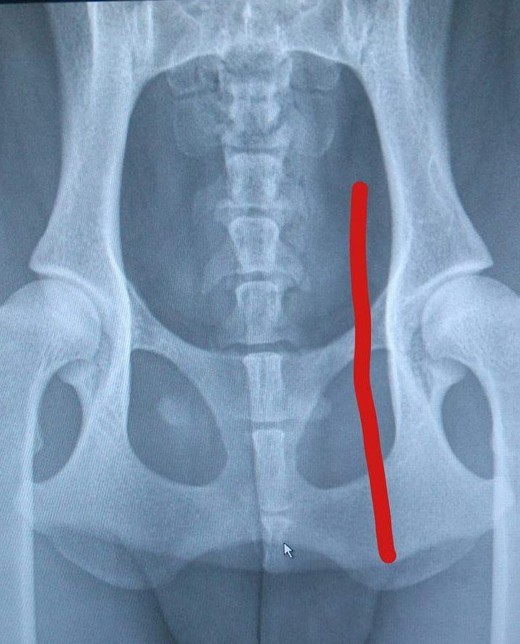

Hunden på bilden är född med 6 svanskotor. Röntgenbilden på henne visar med en rödmarkering vilka kotor som är svanskotor. Det är ju jättesvårt att räkna om man nu inte har en så här fin röntgenbild på sin hunds svanskotor! Hon har alltså 6 st svanskotor och då är det en stubbsvans hon har.